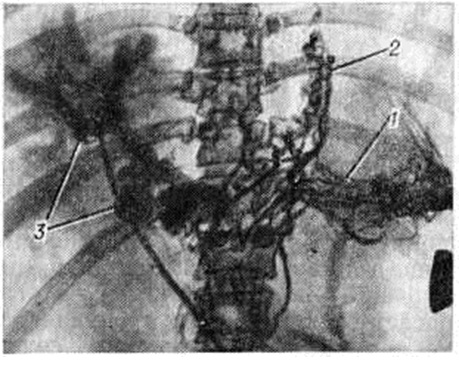

Нередко первым симптомом, выявляющим заболевание (особенно при внепечёночной форме Портальная гипертензия), является случайно обнаруженная увеличенная селезёнка или внезапно возникшее кровотечение из вен пищевода. Больные жалуются на общее недомогание, чувство тяжести в левом подреберье, иногда сопровождающееся болями и повышением температуры, метеоризм, увеличение живота. У больных с асцитом часто выявляются расширенные вены на передней брюшной стенке вокруг пупка (голова медузы) либо по направлению к грудной клетке или надлобковой области (рисунок 2) с характерным при аускультации шумом волчка над ними. Портокавальные анастомозы возникают при внутрипечёночном блоке портальной системы в результате функционирования пупочной вены и обозначаются как синдром Крювелье — Баумгартена (смотри полный свод знаний: Крювелье — Баумгартена синдром). При болезни Киари расширенные вены локализуются чаще по боковым стенкам живота (рисунок 3), на спине и нижних конечностях.

Рис. 2. | ||